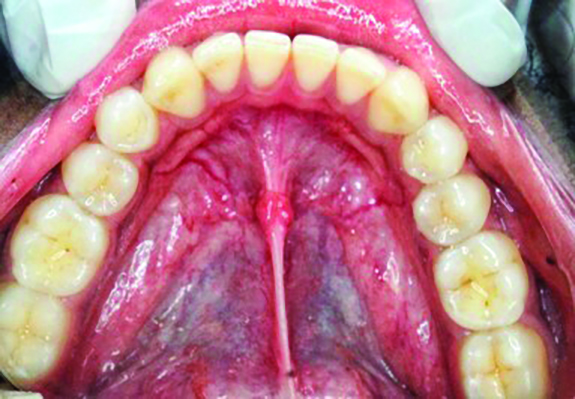

Table 1 presents descriptive statistics for the demographic characteristics of the participants: 83.33% of the study population were aged 18 to 24 years, while 16.66% were aged 25 to 30 years, and 20% of the participants were male while 80% were female, indicating a skewed distribution. Figure 4 through Figure 6 illustrate lingual AG of a representative male subject, and Figure 7 through Figure 9 depict that of a female subject. The mean, standard deviation, mode, median, and extremes for all the mandibular permanent teeth are recorded in Table 2. The extreme measurements were in the range of 0 mm to 10 mm, considering all teeth and subjects. The width of lingual AG varied with each tooth, with the mandibular first molar having the widest average width (6 mm ± 1.3 mm) followed closely by the second molar (5.8 mm ± 1.2 mm). The central incisors (0.5 mm ± 0.5 mm) showed the narrowest zone along with the highest maximum number of teeth without detectable AG (Table 3). The width of AG did not significantly differ between the sexes (Table 4). The overall indicative schematic of lingual AG is shown in Figure 10 and Figure 11.

Fig 7. Lingual attached gingiva in a female subject: Fig 7 = left side, Fig 8 = middle, Fig 9 = right side.

Figure 7

Fig 8. Lingual attached gingiva in a female subject: Fig 7 = left side, Fig 8 = middle, Fig 9 = right side.

Figure 8

Fig 9. Lingual attached gingiva in a female subject: Fig 7 = left side, Fig 8 = middle, Fig 9 = right side.

Figure 9